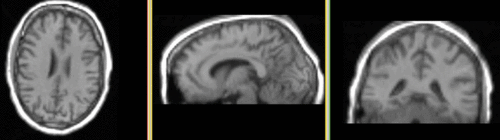

Registration Results

Registered T1 superimposed on DTI registered